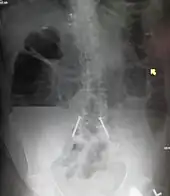

| Upright abdominal X-ray demonstrating a small bowel obstruction. Note multiple air fluid levels. | |

Radiological signs of bowel obstruction include bowel distension and the presence of multiple (more than six) gas-fluid levels on supine and erect abdominal radiographs. Ultrasounds may be as useful as CT scanning to make the diagnosis.[17]